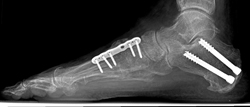

Algunos tipos de osteotomía requieren el uso de injertos de huesos para rellenar huecos y ayudar a que los huesos se suelden. Los tornillos o las placas sostienen los huesos cortados en su lugar mientras se sueldan.

Radiografía lateral del pie de un paciente con una deformidad más grave. Este paciente necesitó una fusión del mediopié además de una transferencia de tendones y un corte en el hueso del talón.